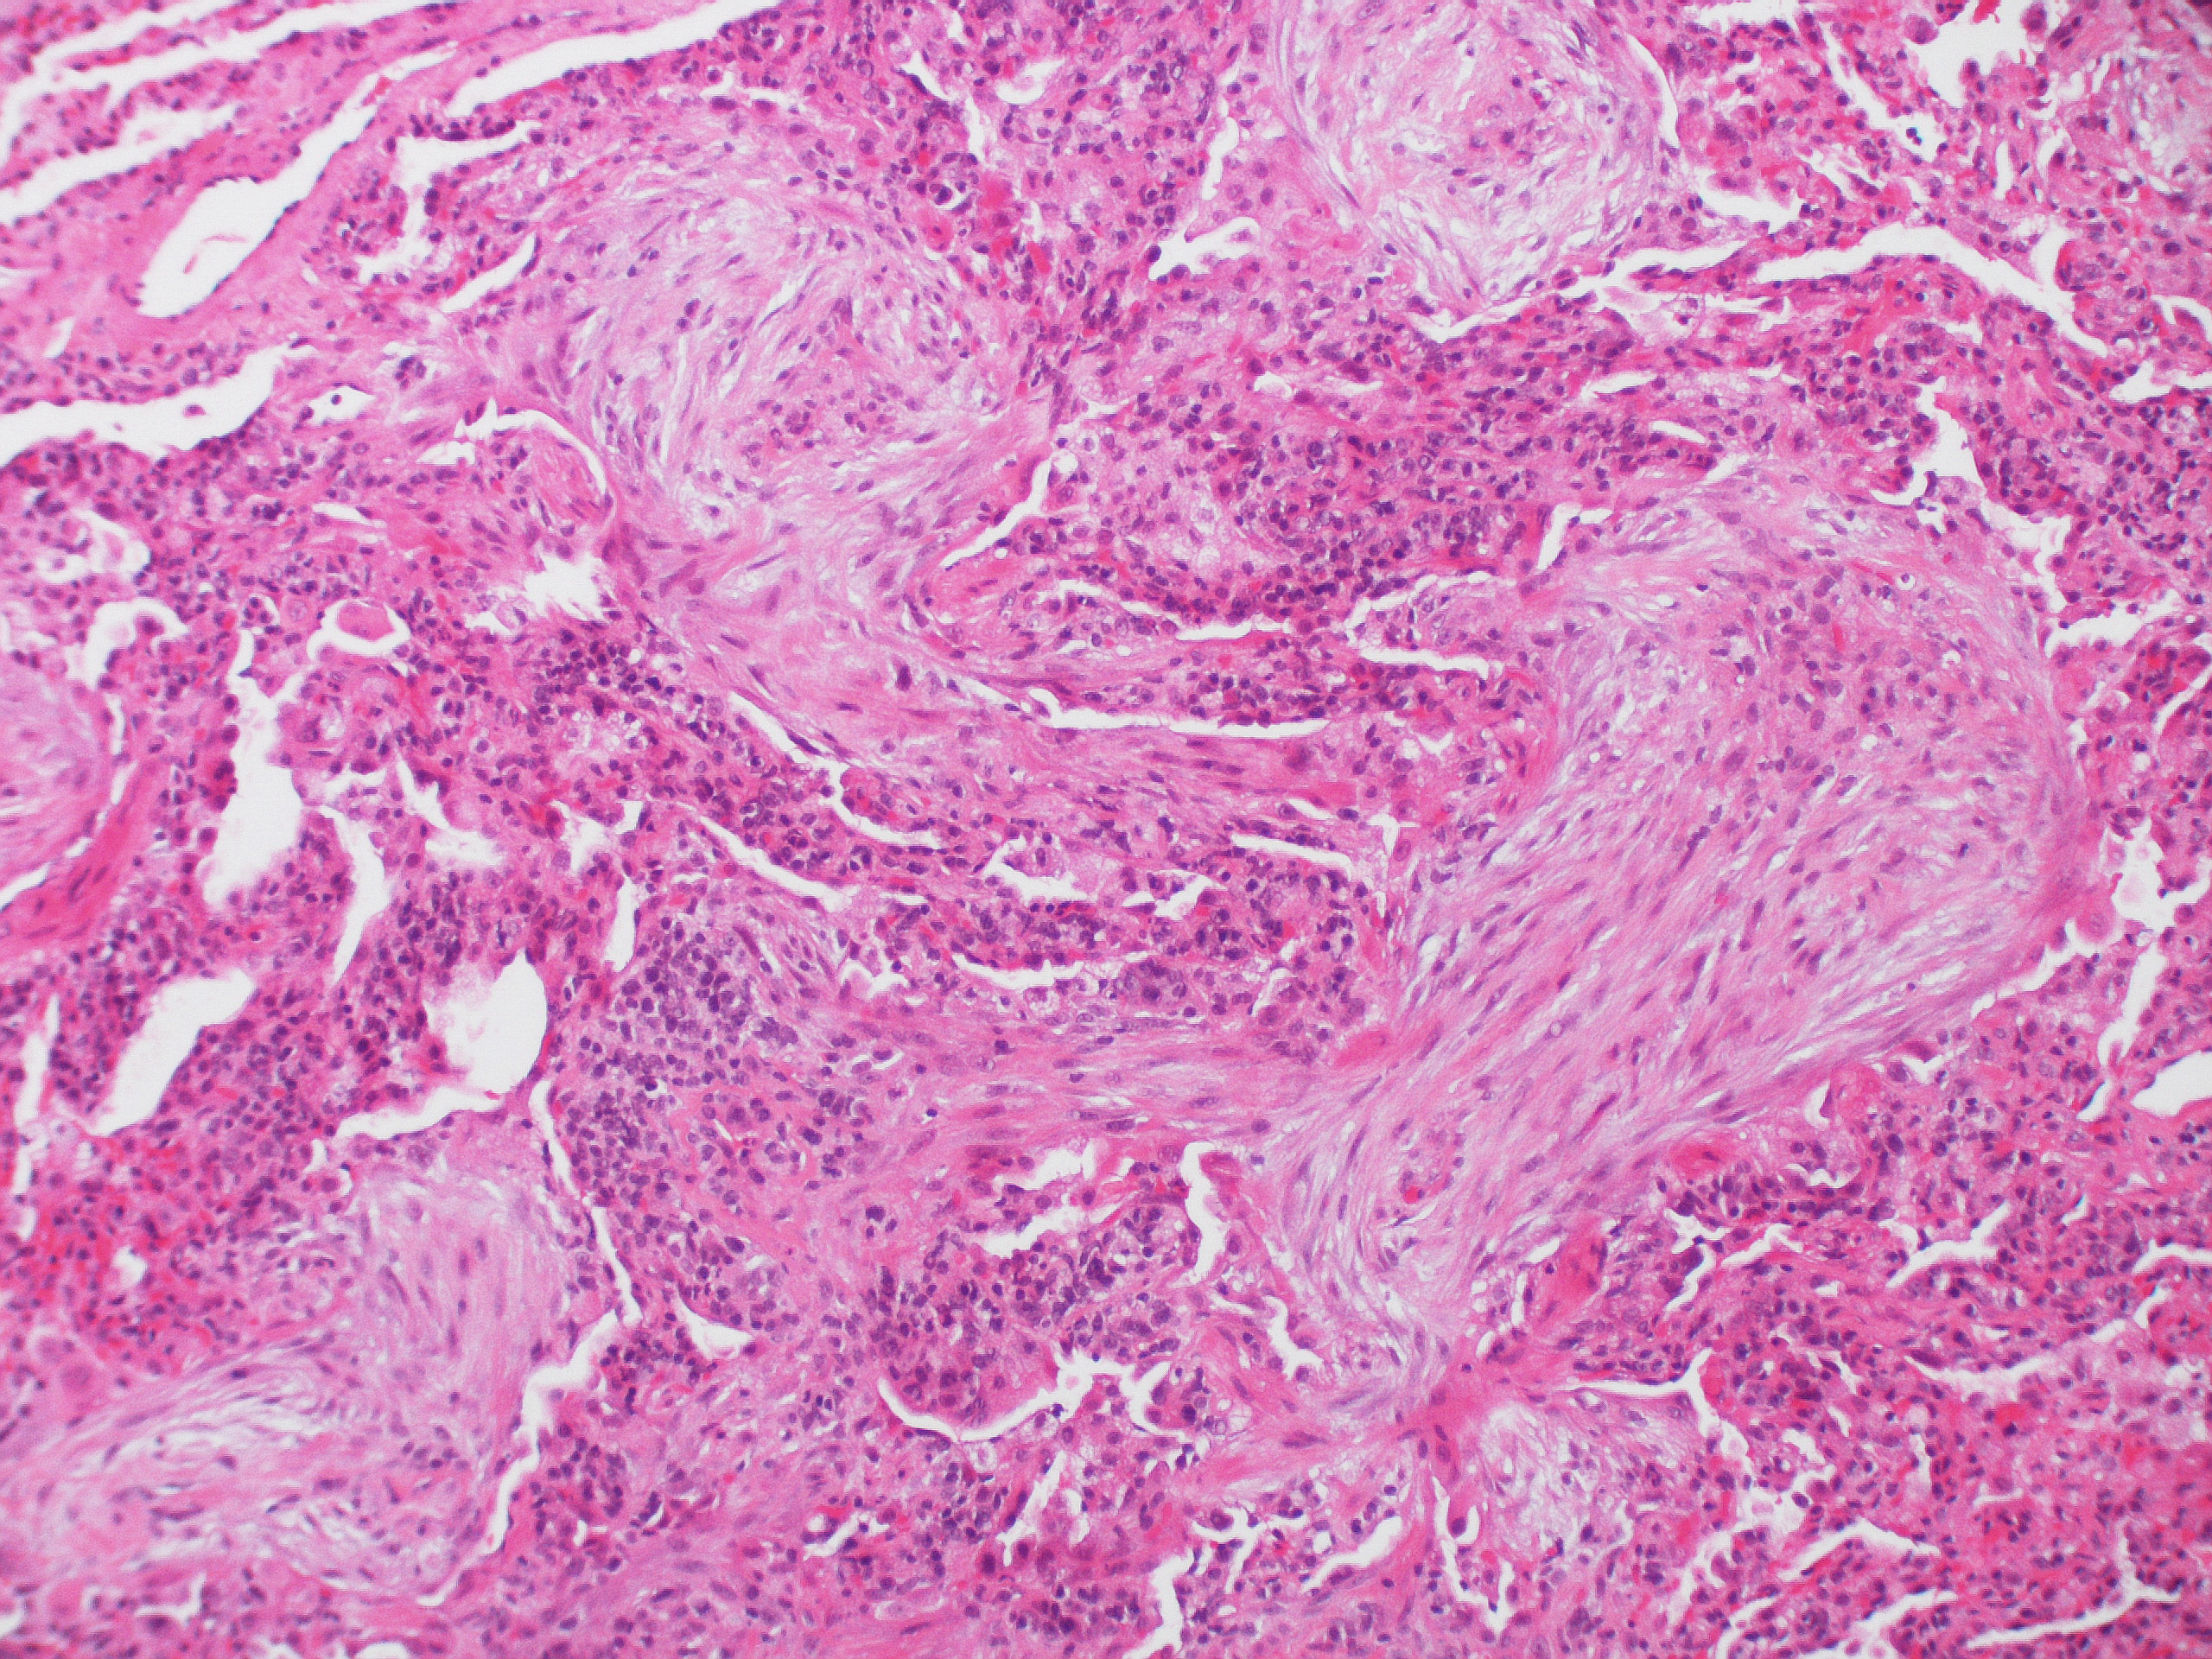

Downregulation of WNT11 is associated with bladder tissue fibrosis in patients with interstitial cystitis/bladder pain syndrome without Hunner lesion

Here, we observed that downregulation of WNT11 is associated with bladder tissue fibrosis in NHIC patients than in HIC patients. Moreover, silencing of WNT family genes in bladder epithelial cells induced fibrotic changes. Higher WNT2B and WNT5A expression was observed in HIC patients than in NHIC patients. WNT11 expression was characteristically down-regulated in NHIC patients. To our knowledge, this is the first study to investigate the relationship between the WNT signalling pathway and bladder tissue fibrosis in IC/BPS patients.

IC is classified into HIC and NHIC. However, whether they belong to the same disease entity is still controversial. In practice, the phenotypes of both types of IC differ. A diagnosis of HIC can be established based on the presence of Hunner’s lesions. However, such lesions are absent in NHIC patients. Therefore, urine or tissue biomarkers may be helpful for the diagnosis of IC. Previously, we observed that NHIC is characterised by severe fibrosis11. Thus, we attempted to identify genes that are associated with fibrosis in NHIC patients.

In this study, WNT11 expression was remarkably repressed in NHIC patients. In our previous study, we observed that NHIC was characterised by severe fibrosis and increased mast cell infiltration, while HIC was characterised by severe inflammation and urothelial denudation in the whole bladder11. These results indicate that the downregulation of WNT11 enhances EMT activation and bladder tissue fibrosis, which is mainly observed in an NHIC bladder. Thus, we propose that inhibition of the WNT11 would be novel pathogenesis and differential diagnosis of NHIC.

In this study, HIC patients had significantly more episodes of urinary frequency (16.1 versus 8.5 times/day, p = 0.006) and lower maximal bladder capacity (208.6 ml versus 361.4 ml, p = 0.006) than NHIC patients. Duration of symptom was significantly shorter (30.9 vs 70.8 months, p = 0.046) in HIC patients. This is probably due to the severity in symptoms, which might have provoked patients to seek earlier medical treatment leading to earlier diagnosis. Conversely, as the symptoms are less severe in NHIC, diagnosis and treatment could be delayed. Therefore, it is important to identify biomarkers that can help diagnose NHIC quickly.

Patients can be easily diagnosed with HIC owing to characteristic symptoms, such as bladder pain and/or urinary urgency/frequency, and Hunner’s lesions observed on cystoscopy. However, if Hunner’s lesions is not observed on cystoscopy and obvious glomerulation or submucosal haemorrhage is not observed during hydrodistention, a diagnosis of NHIC will be difficult to establish. Thus, histopathologic and gene expression studies of a bladder mucosal biopsy sample can aid in the differential diagnosis of IC/BPS by identifying fibrotic changes and WNT-related gene expression levels. Fibrotic changes could be a potential therapeutic target for NHIC. Indeed, in the rat models in our previous study, direct administration of MSCs into the submucosal layer of the bladder significantly restored voiding function and ameliorated tissue fibrosis12,13. These preclinical results indicate that fibrosis of the bladder epithelium may be treatable and require additional clinical trials using stem cells for confirmation. The use of antifibrotic agents, such as NAC, which was effective in an IC rat model, may be helpful for treating fibrosis in NHIC patients27.